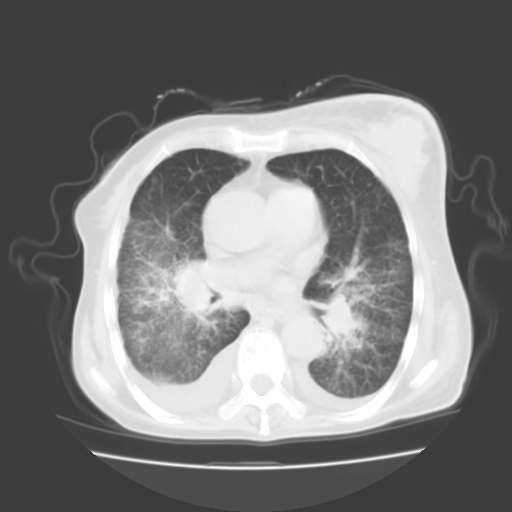

女70y乳腺ca(针吸活检)

1)左侧乳腺癌并左侧腋窝及纵隔淋巴结转移,两肺淋巴道转移(癌性淋巴管炎),肝脏多发性转移。2)双侧胸腔积液。3)慢性胆囊炎。

癌性淋巴管炎,胸膜转移.肝内转移,纵隔及腋窝淋巴结转移

2、左腋窝、纵隔淋巴结肿大(转移性);

3、双肺癌性淋巴管炎;

4、双侧胸腔积液(考虑淋巴回流障碍所致);